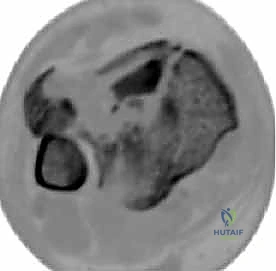

2. التصوير المقطعي المحوسب (CT Scan) - المعيار الذهبي

لا يمكن إجراء جراحة حديثة لكسر البيلون دون إجراء أشعة مقطعية. لماذا؟

كشفت الأبحاث المتقدمة (مثل أبحاث كول Cole وزملائه) والتي يعتمد عليها الدكتور هطيف، أن الأشعة المقطعية، وخاصة مع إعادة البناء ثلاثي الأبعاد (3D Reconstruction)، تسمح برسم خريطة دقيقة لكل قطعة عظمية مفتتة في السطح المفصلي (AO/OTA 43-C3).

تظهر الأشعة المقطعية النمط الثابت لتفتت البيلون والذي يتكون عادة من ثلاث قطع رئيسية:

* القطعة الأمامية الجانبية (Chaput fragment): متصلة بالرباط الظنبوبي الشظوي الأمامي.

* القطعة الخلفية (Volkmann fragment): متصلة بالرباط الظنبوبي الشظوي الخلفي.

* القطعة الأنسية (Medial Malleolus): متصلة بالرباط الدالي.

وفي الوسط، توجد منطقة "الانهيار المفصلي" (Die-punch fragment) التي تُدفع داخل العظم.

يستخدم الأستاذ الدكتور محمد هطيف هذه الخريطة المقطعية لتحديد مسار الشقوق الجراحية، واختيار أحجام وأنواع الشرائح المعدنية المطلوبة، وتحديد تسلسل إرجاع القطع العظمية قبل دخول غرفة العمليات.